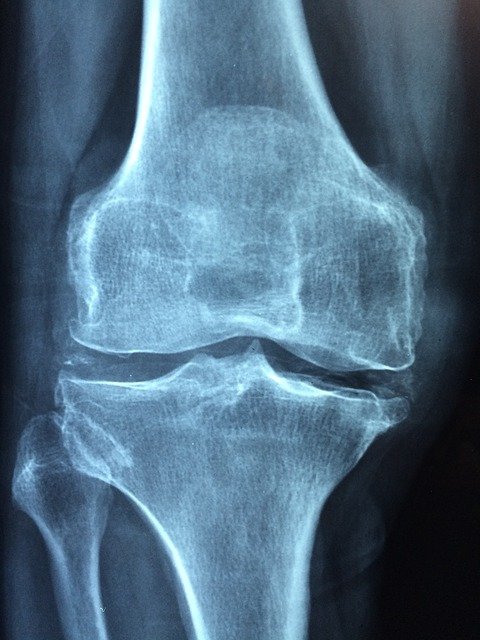

Faktanya, osteoporosis yang menyebabkan tulang menjadi keropos tidak 100% disebabkan oleh defisiensi kalsium. Faktor penyerapan kalsium juga sangat berpengaruh. Ternyata, kalsium yang masuk ke dalam tubuh tidak dapat langsung diserap oleh tulang.

Apa saja penyebab tulang keropos atau osteoporosis? Sejumlah hal berikut termasuk dalam faktor yang menimbulkan masalah pada tulang.

Penyebab lainnya adalah kurangnya asupan magnesium dan fosfor pada tubuh. Dikutip dari NCBI, defisiensi magnesium dapat menyebabkan hipomagnesemia yang berkontribusi terhadap kurangnya kepadatan tulang. Selain itu, kekurangan magnesium juga memengaruhi kekakuan tulang.

Zat lain yang dibutuhkan oleh tubuh dalam mendukung pemeliharaan tulang adalah fosfor. Bekerjasama dengan kalsium, fosfor membantu menjaga bone mineral density (BMD). Selain dari sumber makanan, pastikan juga pasta gigi Anda mengandung fosfor untuk kesehatan tulang gigi Anda!